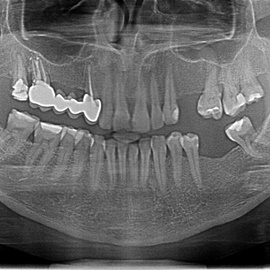

Pacjent z długą historią leczenia implantologicznego. Pierwsze implanty w pozycjach 23, 24 miał wkręcane w Warszawie przed 25 laty. Implant w pozycji górnego prawego kła ma agresywny gwint, ponieważ bezpośrednio po implantacji był obciążony (immediate loading) tymczasowym atachmentem ball abutmentv do stabilizacji tymczasowej protezy ruchomej. Kość szczęki regenerowana i odbudowywana etapami w całym górnym prawym kwadrancie. Pacjent planuje uzupełnić brakujące zęby 25, 26.